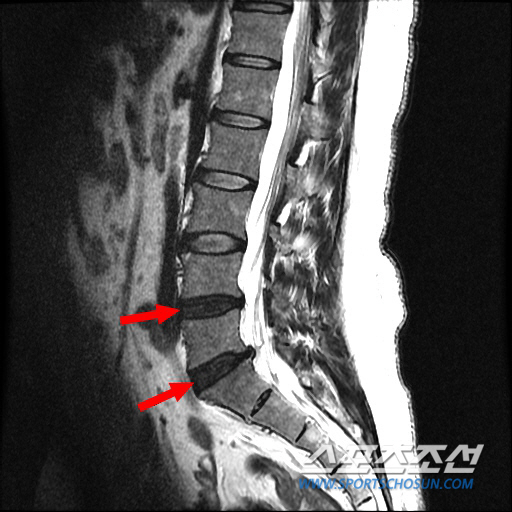

디스크 내장증은 척추 뼈 사이에서 완충역할을 하는 디스크가 외부 충격으로 손상돼 면역체계와 신경 등을 자극하면서 통증을 일으키는 질환이다. 디스크 내부가 손상됐기 때문에 X-ray나 MRI상으로는 정상으로 보일 수 있다. 디스크가 돌출돼 신경근을 압박하지 않기 때문에 다리가 저린 증상도 없다.

허리디스크 환자처럼 앉아 있는 것이 힘들고, 허리를 굽히면 통증이 심해진다. 하지만 허리디스크 환자와 달리 감각마비나 근력약화 등 신경증상이 없고 누워서 다리를 편 채로 들어 올려도 정상 소견을 보이기도 한다.